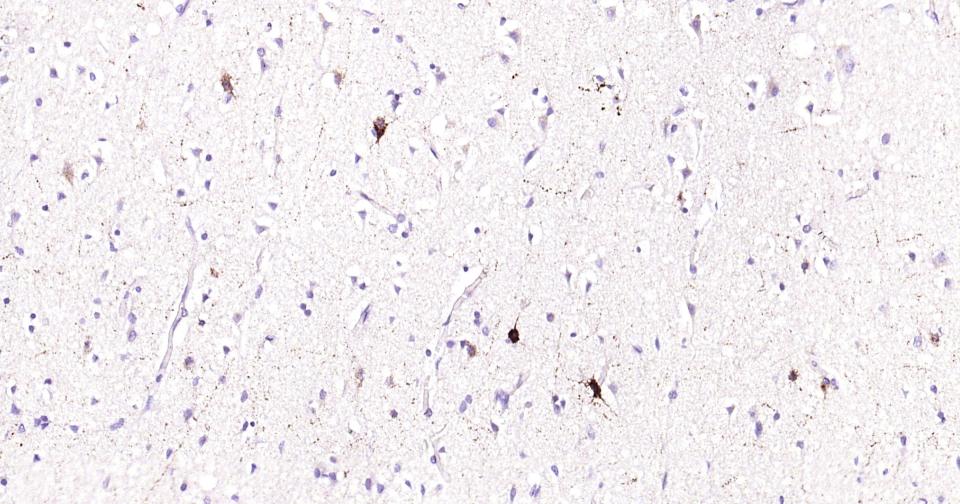

IHC-PHuman, Mouse, Rat1:50-200

IHC-FHuman, Mouse, Rat1:50-200

IFHuman, Mouse, Rat1:50-200

交叉反应: Human, Mouse, Rat